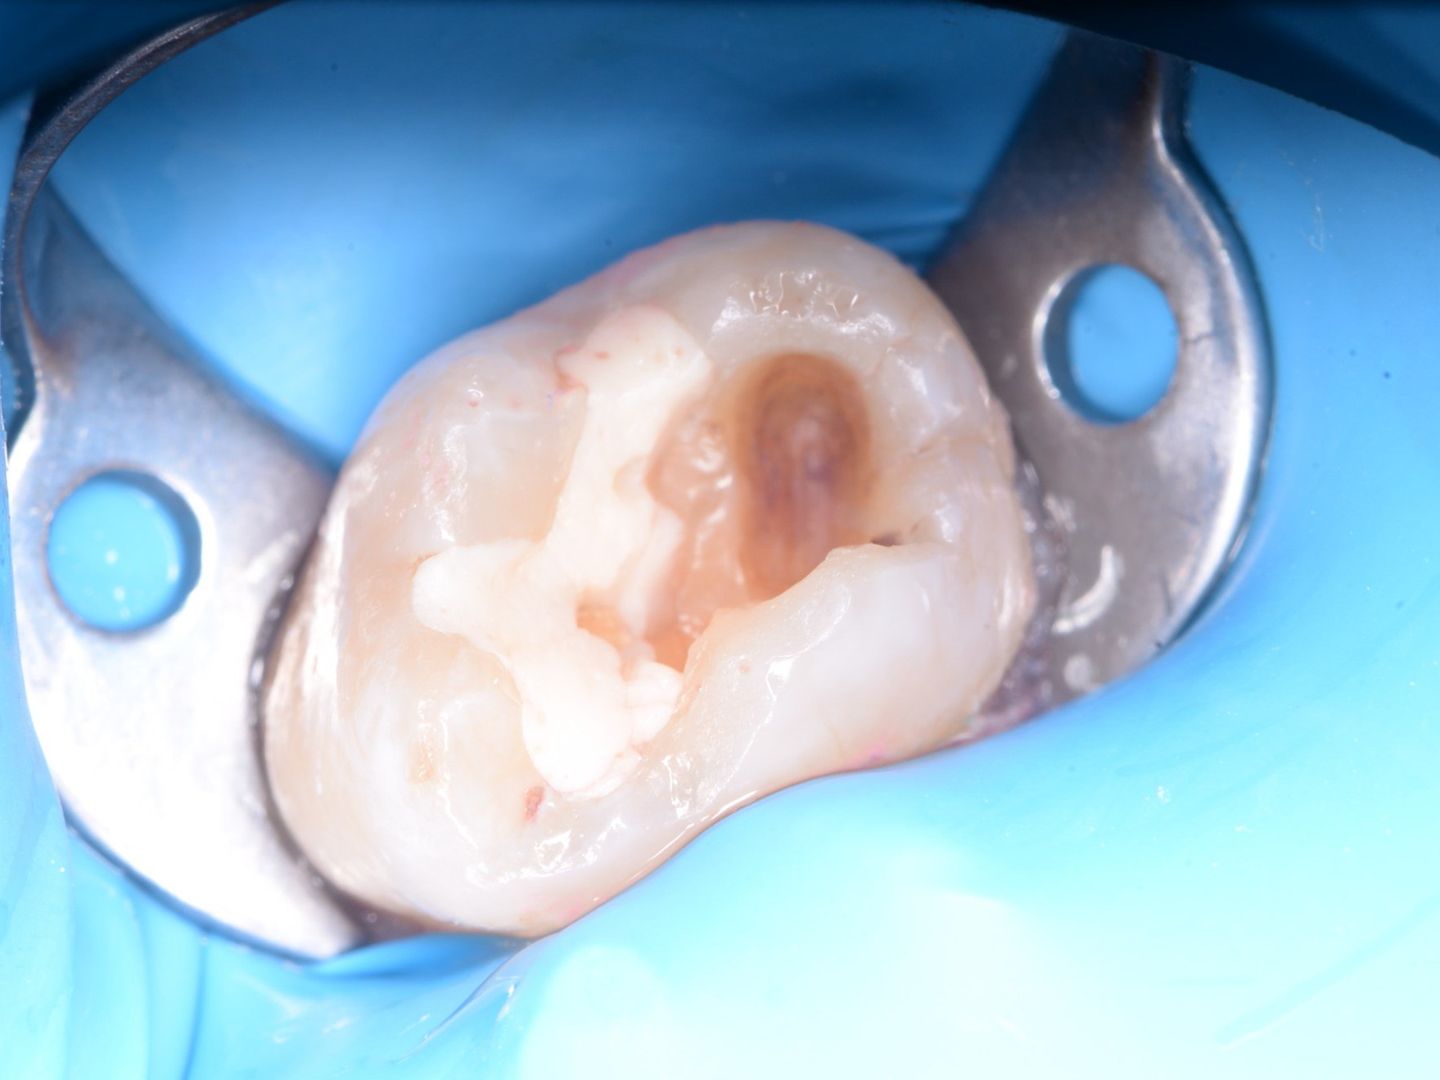

Специализируюсь на лечении зубов с применением дентального микроскопа.

• Лечением кариозных поражений всех стадий, а также их осложнений, таких как пульпиты и периодонтиты.

• Восстановлением разрушенных зубов с последующей подготовкой их под ортопедические конструкции.